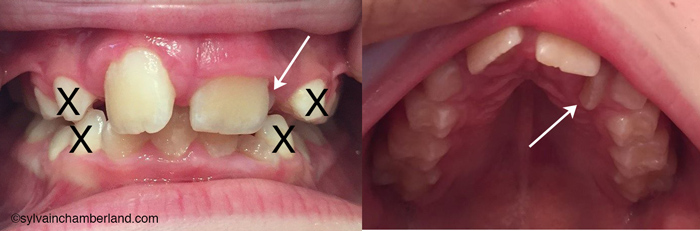

Je constate que l’incisive latérale supérieure gauche (flèche) fait éruption au palais en articulé croisé avec la canine primaire inférieure. Sur la photo de gauche, je constate que les dents supérieures postérieures sont à l’extérieure des dents postérieures inférieures. Il n’y a pas d’articulé croisé postérieur.

Je crois qu’il est indiqué de procéder à l’extraction des 4 canines primaires (marquée d’un X) afin de faciliter l’alignement des dents antérieures et éviter l’articulé croisé 22/73.

Une expansion est possiblement indiquée. Si tel est le cas, je recommande un disjoncteur fixe. Un appareil d’expansion amovible ne produit pas une expansion de l’os basal et favorise une bascule des dents postérieures.

Toutefois, étant donné que votre fils a déjà subi de l’expansion et que l’extraction des canines primaires permettrait un meilleur alignement des incisives, je procéderais aux extractions des dents primaires et révaluerais dans 6 mois. Il sera toujours temps de faire de l’expansion.